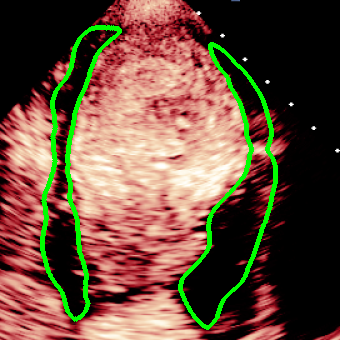

For variations caused by low quality images such as those of low resolution or significant artifacts, however, the unique ground truth may not be available. Take the myocardial segmentation task of Myocardial Contrast Echocardiography (MCE) as an example. An inter-observer experiment was conducted among five experienced cardiologists, and Fig. 1(a)(b) visualize the annotations of two images from three of these cardiologists. It can be seen that the labels by different cardiologists vary significantly, especially in locations where the intensity information of myocardium is very similar to the background. Table 1 shows the average Dice of the annotation of each cardiologist, using one of the others’ as the ground truth, over 180 images. We can observe that none of the Dice is above 0.9, some even under 0.8, confirming significant variations among the annotations. In this case, as the variations are caused by the image quality, even these cardiologists cannot tell which annotation is better than others, and a majority vote for ground truth would not make sense sometimes as can be seen in Fig. 1(c)(d). For this reason, we cannot obtain a unique ground truth in the evaluation process and the traditional metrics such as Dice and IoU cannot be used.